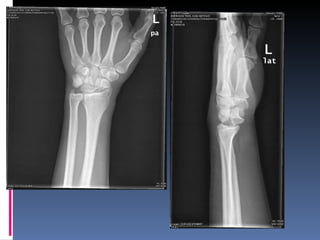

Varon 46 años, sin AP de interes MC: Caida accidental sobre muñeca dcha Rx  urgencias: imagen compatible con solución de continuidad en la cortical de la estiloides radial Trat: ferula dorsal y revision en 10 dias en CCEE traumatologia.

5 semanas después:  CCEE traumatologia HARE Guadix: se retira férula, movilizacion aún dolorosa, limitacion de La flexoextension por dolor. Alta médica.  4 semanas después:  Se solicita TC: luxacion semilunar. Traslado a Unidad mano traumatologia HUVN HUVN: Se interviene quirúrgicamente intentando en un primer momento la reducción del semilunar. Posteriormente se realiza carpectomía de la primera hilera del carpo por la imposibilidad de reducción  Actualmente en RHB con grave limitación funcional

Varon 46 años,sin AP de interes MC: Caida accidental sobre muñeca dcha Rx urgencias: imagen compatible con solución de continuidad en la cortical de la estiloides radial Trat: ferula dorsal y revision en 10 dias en CCEE traumatologia.